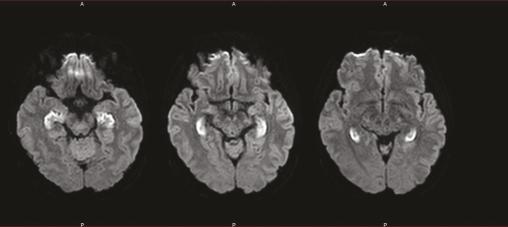

IRM cérébrale en séquence de diffusion. Coupes axiales sur les hippocampes révélant des lésions toxiques dues aux opioïdes et provoquant une amnésie hippocampique.